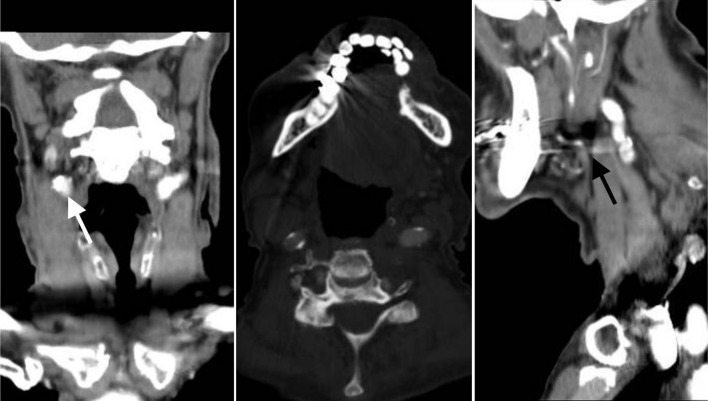

Internal carotid artery webs (ICAWs) have been described as noninflammatory, nonatherosclerotic shelf-like projections of intimal fibrous tissue which may be the culprit for embolic stroke of unknown origin. Carotid webs are an atypical form of intimal fibromuscular dysplasia (FMD) and internal carotid webs create areas of stagnation and recirculation distal to the web that favor thrombus formation and embolism. Symptomatic carotid webs are conventionally associated with young women presenting with few vascular risk factors and < 50% stenosis in the affected ICA. ICAWs are being described more and more in the vascular literature, but the management of this pathology remains unclear. We describe a rare case of a 90-year-old male who presented with a significantly sclerosed symptomatic right ICAW without evidence of comorbid atherosclerotic disease. The clinical management, intraoperative findings, and postoperative course are described herein. At the age of 90, this patient is the oldest case of symptomatic carotid web recorded in the literature. Successful management with a carotid endarterectomy is an appropriate strategy for treatment even in a nonagenarian. We would favor carotid endarterectomy over carotid artery stenting given the circumferential, fibrotic nature of these lesions.